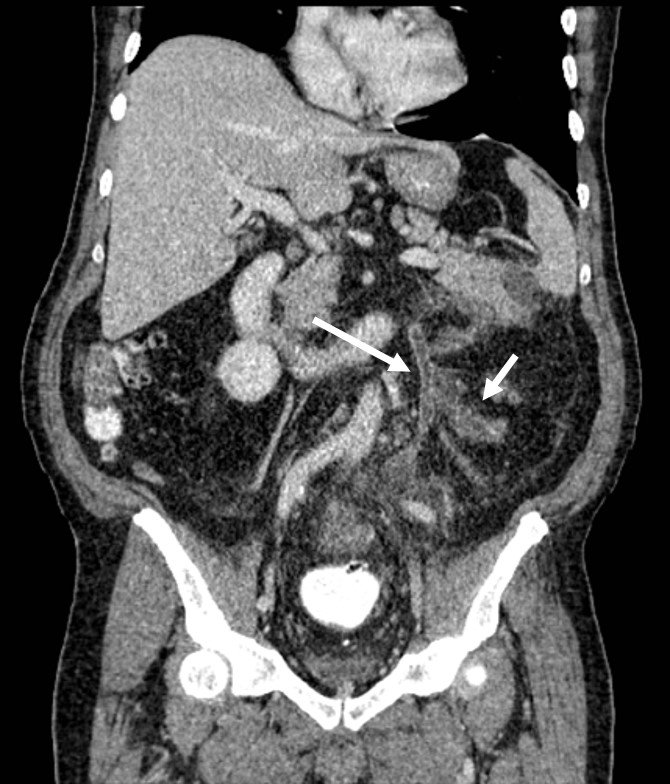

Además, se identificó trombosis de la vena mesentérica inferior y sus afluentes, la vena cólica izquierda y vena rectal superior, con marcado aumento en su calibre, engrosamiento e irregularidad de sus paredes, además de estriación de la grasa circundante, hallazgos compatibles con tromboflebitis (Figs. 2, 3 y 4).